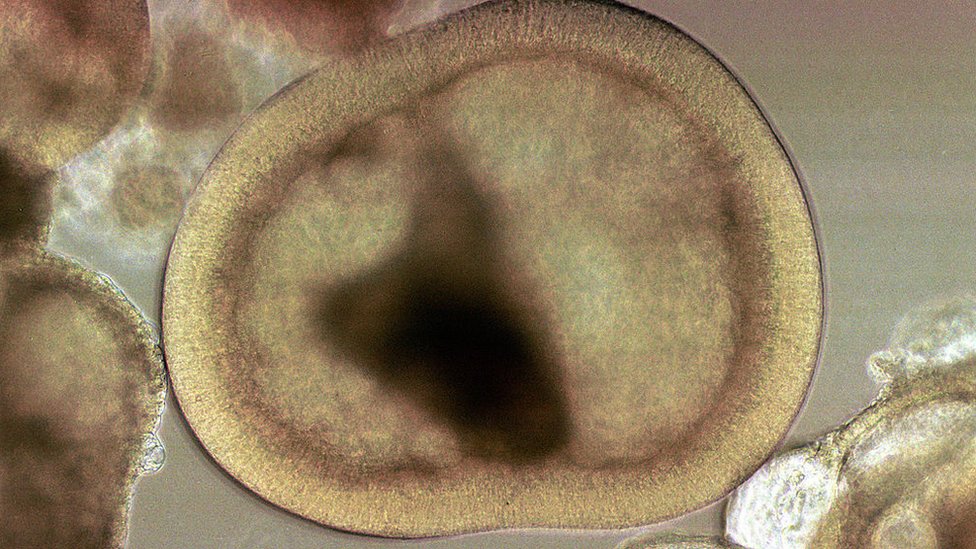

Las células madre embrionarias, que se extraen de un embrión en crecimiento, tienen la ventaja natural de poder dar lugar a cualquier otra célula del cuerpo, un atributo conocido como pluripotencia.

Pero hay quien ha planteado objeciones éticas al uso de embriones para obtener estas células madre, lo que se elude con el uso de células madre extraídas de tejidos adultos.